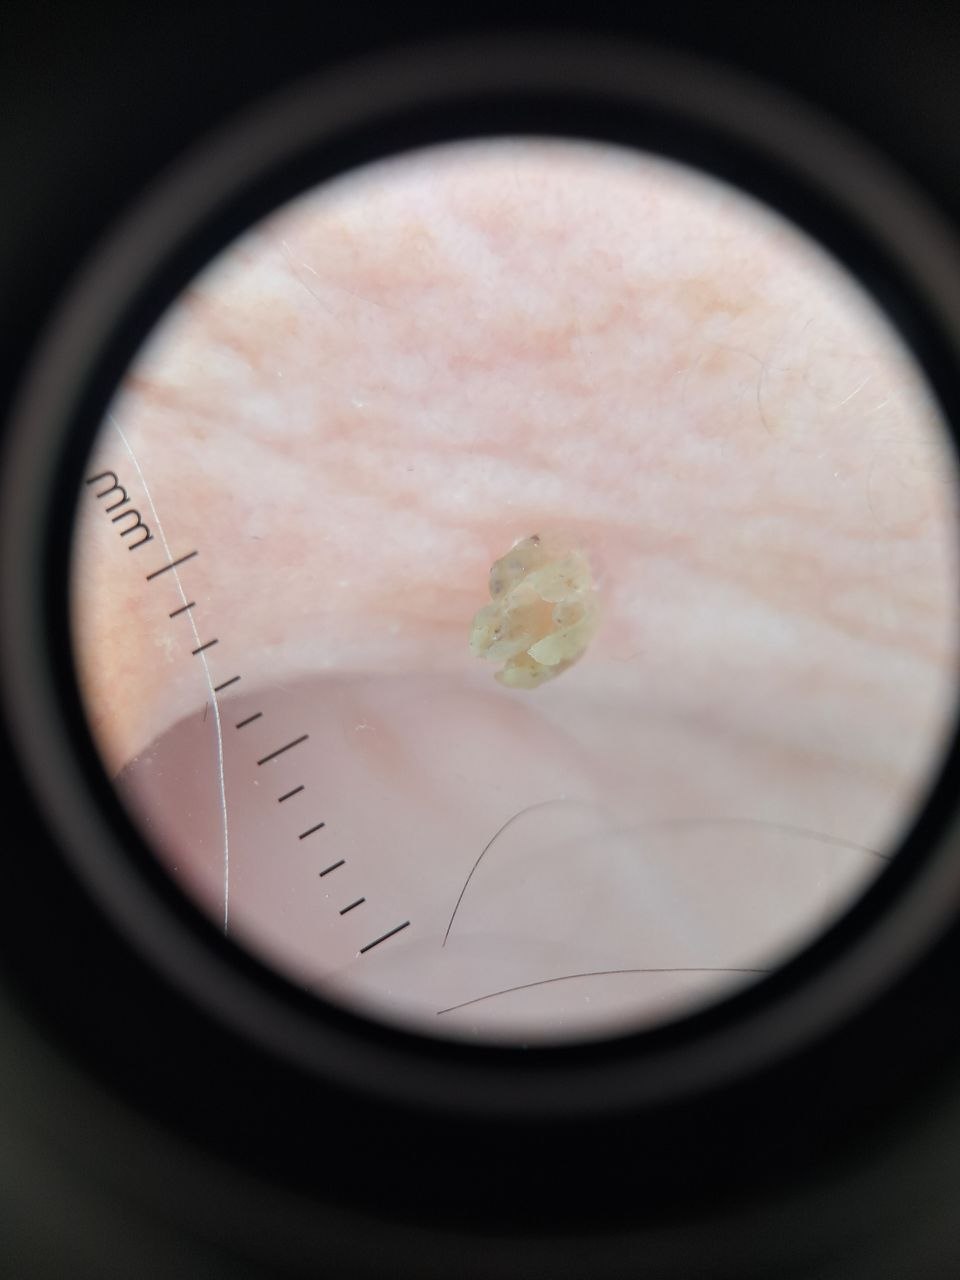

Мы всё чаще начали встречать пациентов в Бендерах с подобными образованиями. Роговая кератома это плотное кожное образование, которое со временем может напоминать небольшой «рог». Чаще всего появляется на участках кожи, подверженных солнцу, и связана с возрастными изменениями.

Несмотря на пугающий внешний вид, такие образования обычно доброкачественные и легко удаляются лазером. Но важно помнить: иногда под ними могут скрываться более серьёзные процессы.